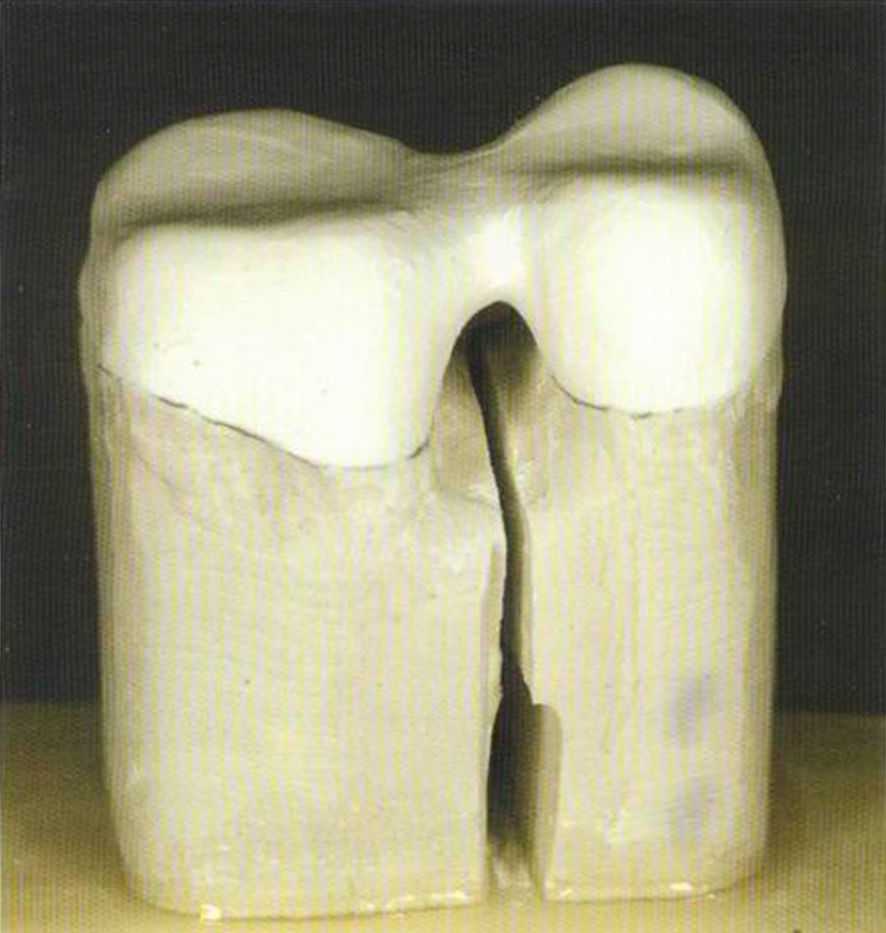

Соотношение размеров готовых вкладок и спички. Они маленькие, но требуют много работы и могут быть очень полезны пациенту.

Вкладки все еще выглядят очень грубо. После фиксации в полости рта их надо препарировать.